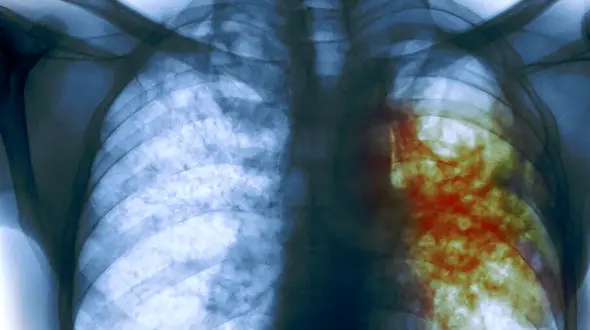

رکنا: سل، بیماری عفونی و واگیری که بر ریهها و سایر اعضای بدن تأثیر میگذارد، سالانه میلیونها نفر را مبتلا و جان هزاران نفر را میگیرد، در حالی که با آگاهی، پیشگیری و درمان مناسب قابل کنترل است.

رکنا: سل یک بیماری عفونی است که به وسیله باکتری مایکوباکتریوم توبرکلوزیس ایجاد میشود. این باکتری معمولاً از طریق هوا (قطرات معلق در هوا ناشی از سرفه، عطسه، صحبت کردن یا آواز خواندن فرد مبتلا) منتقل…

رکنا: علائم ابتلا به سل را در ادامه بخوانید.